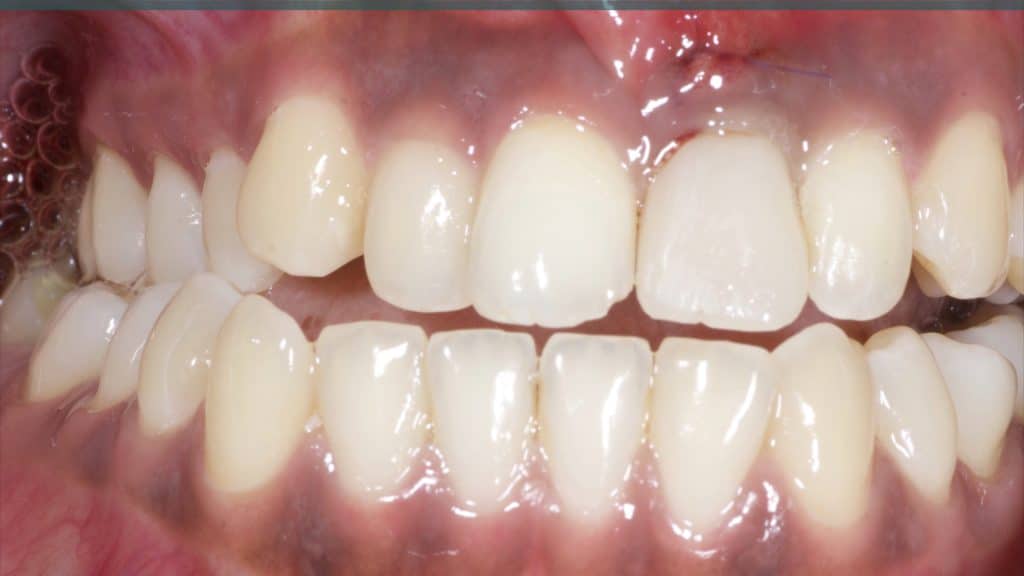

20 days post-op after suture removal